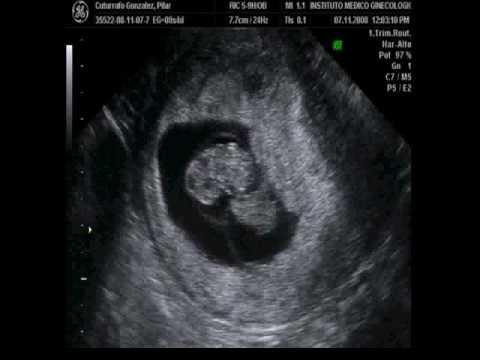

Ecografía gemelar de 8 semanas

Explora imágenes de ecografías gemelares de 8 semanas, ideales para ver el desarrollo temprano de los bebés y compartir momentos especiales.